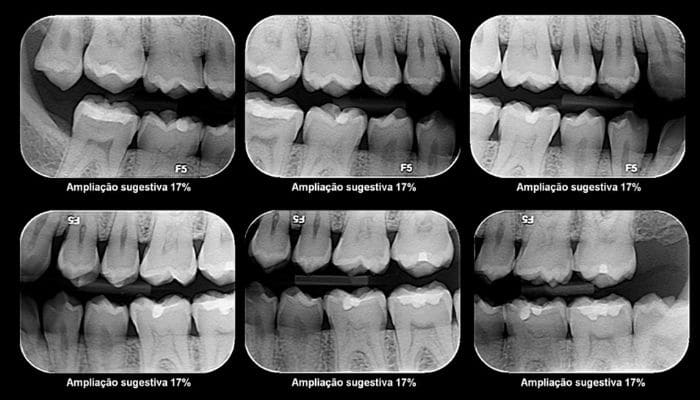

O raio X panorâmico, também conhecido como ortopantomografia ou radiografia panorâmica, é um exame que mostra todos os ossos da região da boca e suas articulações, além de todos os dentes, até mesmo aqueles que ainda não nasceram, sendo um ótimo auxiliar na área da odontologia para planejar melhor o tratamento.

1 – Seve para contar a quantidade de dentes presentes e dentro dos maxilares, como dentes retidos, por exemplo, e identificar dentes ausentes;

2 – Identificar o contorno da mandíbula e avaliar a densidade óssea e a posição do canal de nervo dos dentes inferiores;

3 Observar a quantidade de osso restante na doença periodontal, entre outros…

Através do raio-X o dentista consegue planejar o tratamento mais adequado para cada pessoa